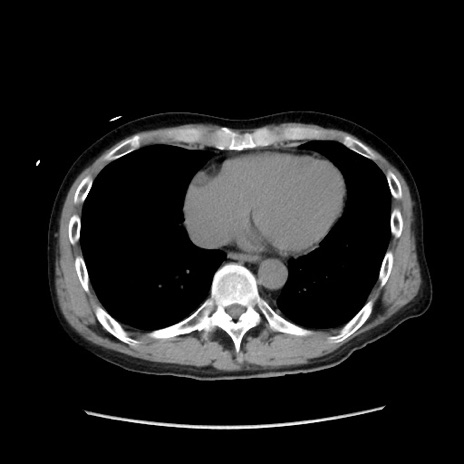

冠状断像

症例37(横断像)

【症例】40歳代 男性

【主訴】腹痛

【現病歴】4時間ほど前に電車に乗車中に臍部上より腹痛出現。徐々に増悪し起立困難となり、救急外来受診。生ものは数日食べていない。今朝お雑煮を食べた。

【身体所見】BT 36.8℃、BP 117/84mmHg、HR 91/min、SpO2 97%、苦悶様、腹部:臍上部広範囲圧痛あり、反跳痛±

【データ】WBC 8100、CRP 0.03